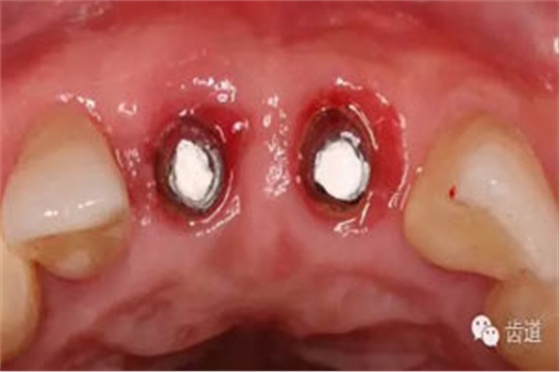

半年后復(fù)診

Cbct影像

袖口形態(tài)